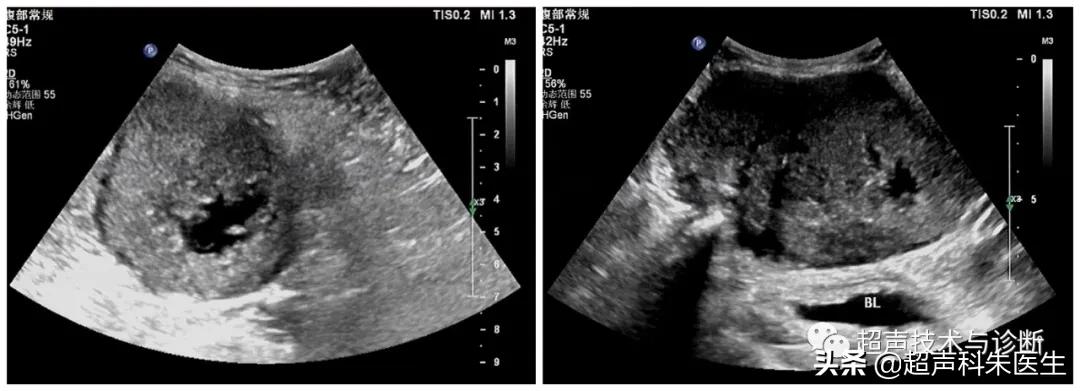

宽景成像显示包块大体样貌

超声所见:下腹部腹膜外探及一低回声团块,大小12.4*6.9*9.0cm,边界清楚,内部回声不均质,内见散在点状强回声及小片状无回声区,包块与腹直肌分界不清,CDFI观察:其内可见少量血流信号。